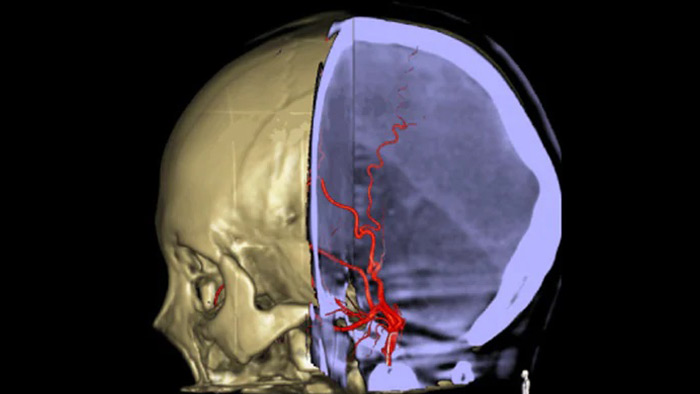

SmartCT Vaso IV

Comprobar la ubicación y la longitud del coágulo

SmartCT Vaso permite la visualización más allá del coágulo con imágenes periprocedimiento de las caras distales de los vasos en el accidente cerebrovascular isquémico. SmartCT Vaso es una técnica de adquisición basada en una TC de haz cónico y una inyección de contraste intrarterial. Permite la visualización más allá del coágulo con imágenes periprocedimiento de las caras distales de los vasos en el accidente cerebrovascular isquémico. Mediante el llenado retrógrado, se ven las estructuras de los vasos antes y después del coágulo. SmartCT Vaso 3D Roadmap puede utilizarse para visualizar los dispositivos de recuperación de coágulos.